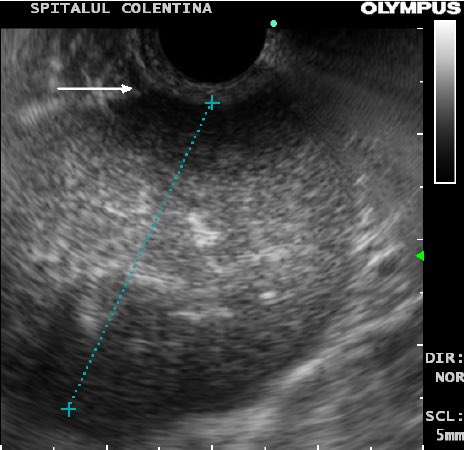

يتم فحص هذه التغيرات عن طريق التنظير الصوتي للورم.

في حالة وجود بعض الدلائل على تغير سرطاني داخل الورم، يفضل ازالته جراحيًا لتفادي انتشار الخلايا السرطانية اثناء الإزالة بالمنظار. الصور التالية هي لأحد الأورام التي تم ازالتها بيد الدكتور أشرف مغربي @AshrafMaghrabi. شكرا له لمشاركتي الصور